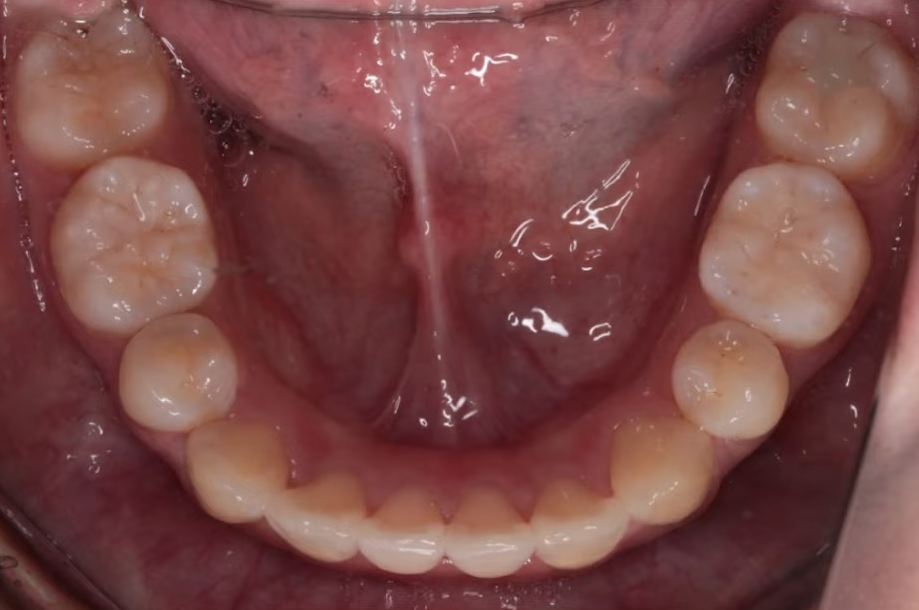

뻐드러져 있던 치아 배열 모습이 정상적으로 돌아온 걸 확인하실 수 있을 겁니다.

기울어졌던 앞니가 정상 각도로 줄어들었고 자연스레 돌출입도 개선된 걸 볼 수 있지요.

입술 라인도 부드럽고 자연스럽게 닫히며,

잇몸 노출도 줄어들어 웃는 인상까지 부드러워졌는데요.